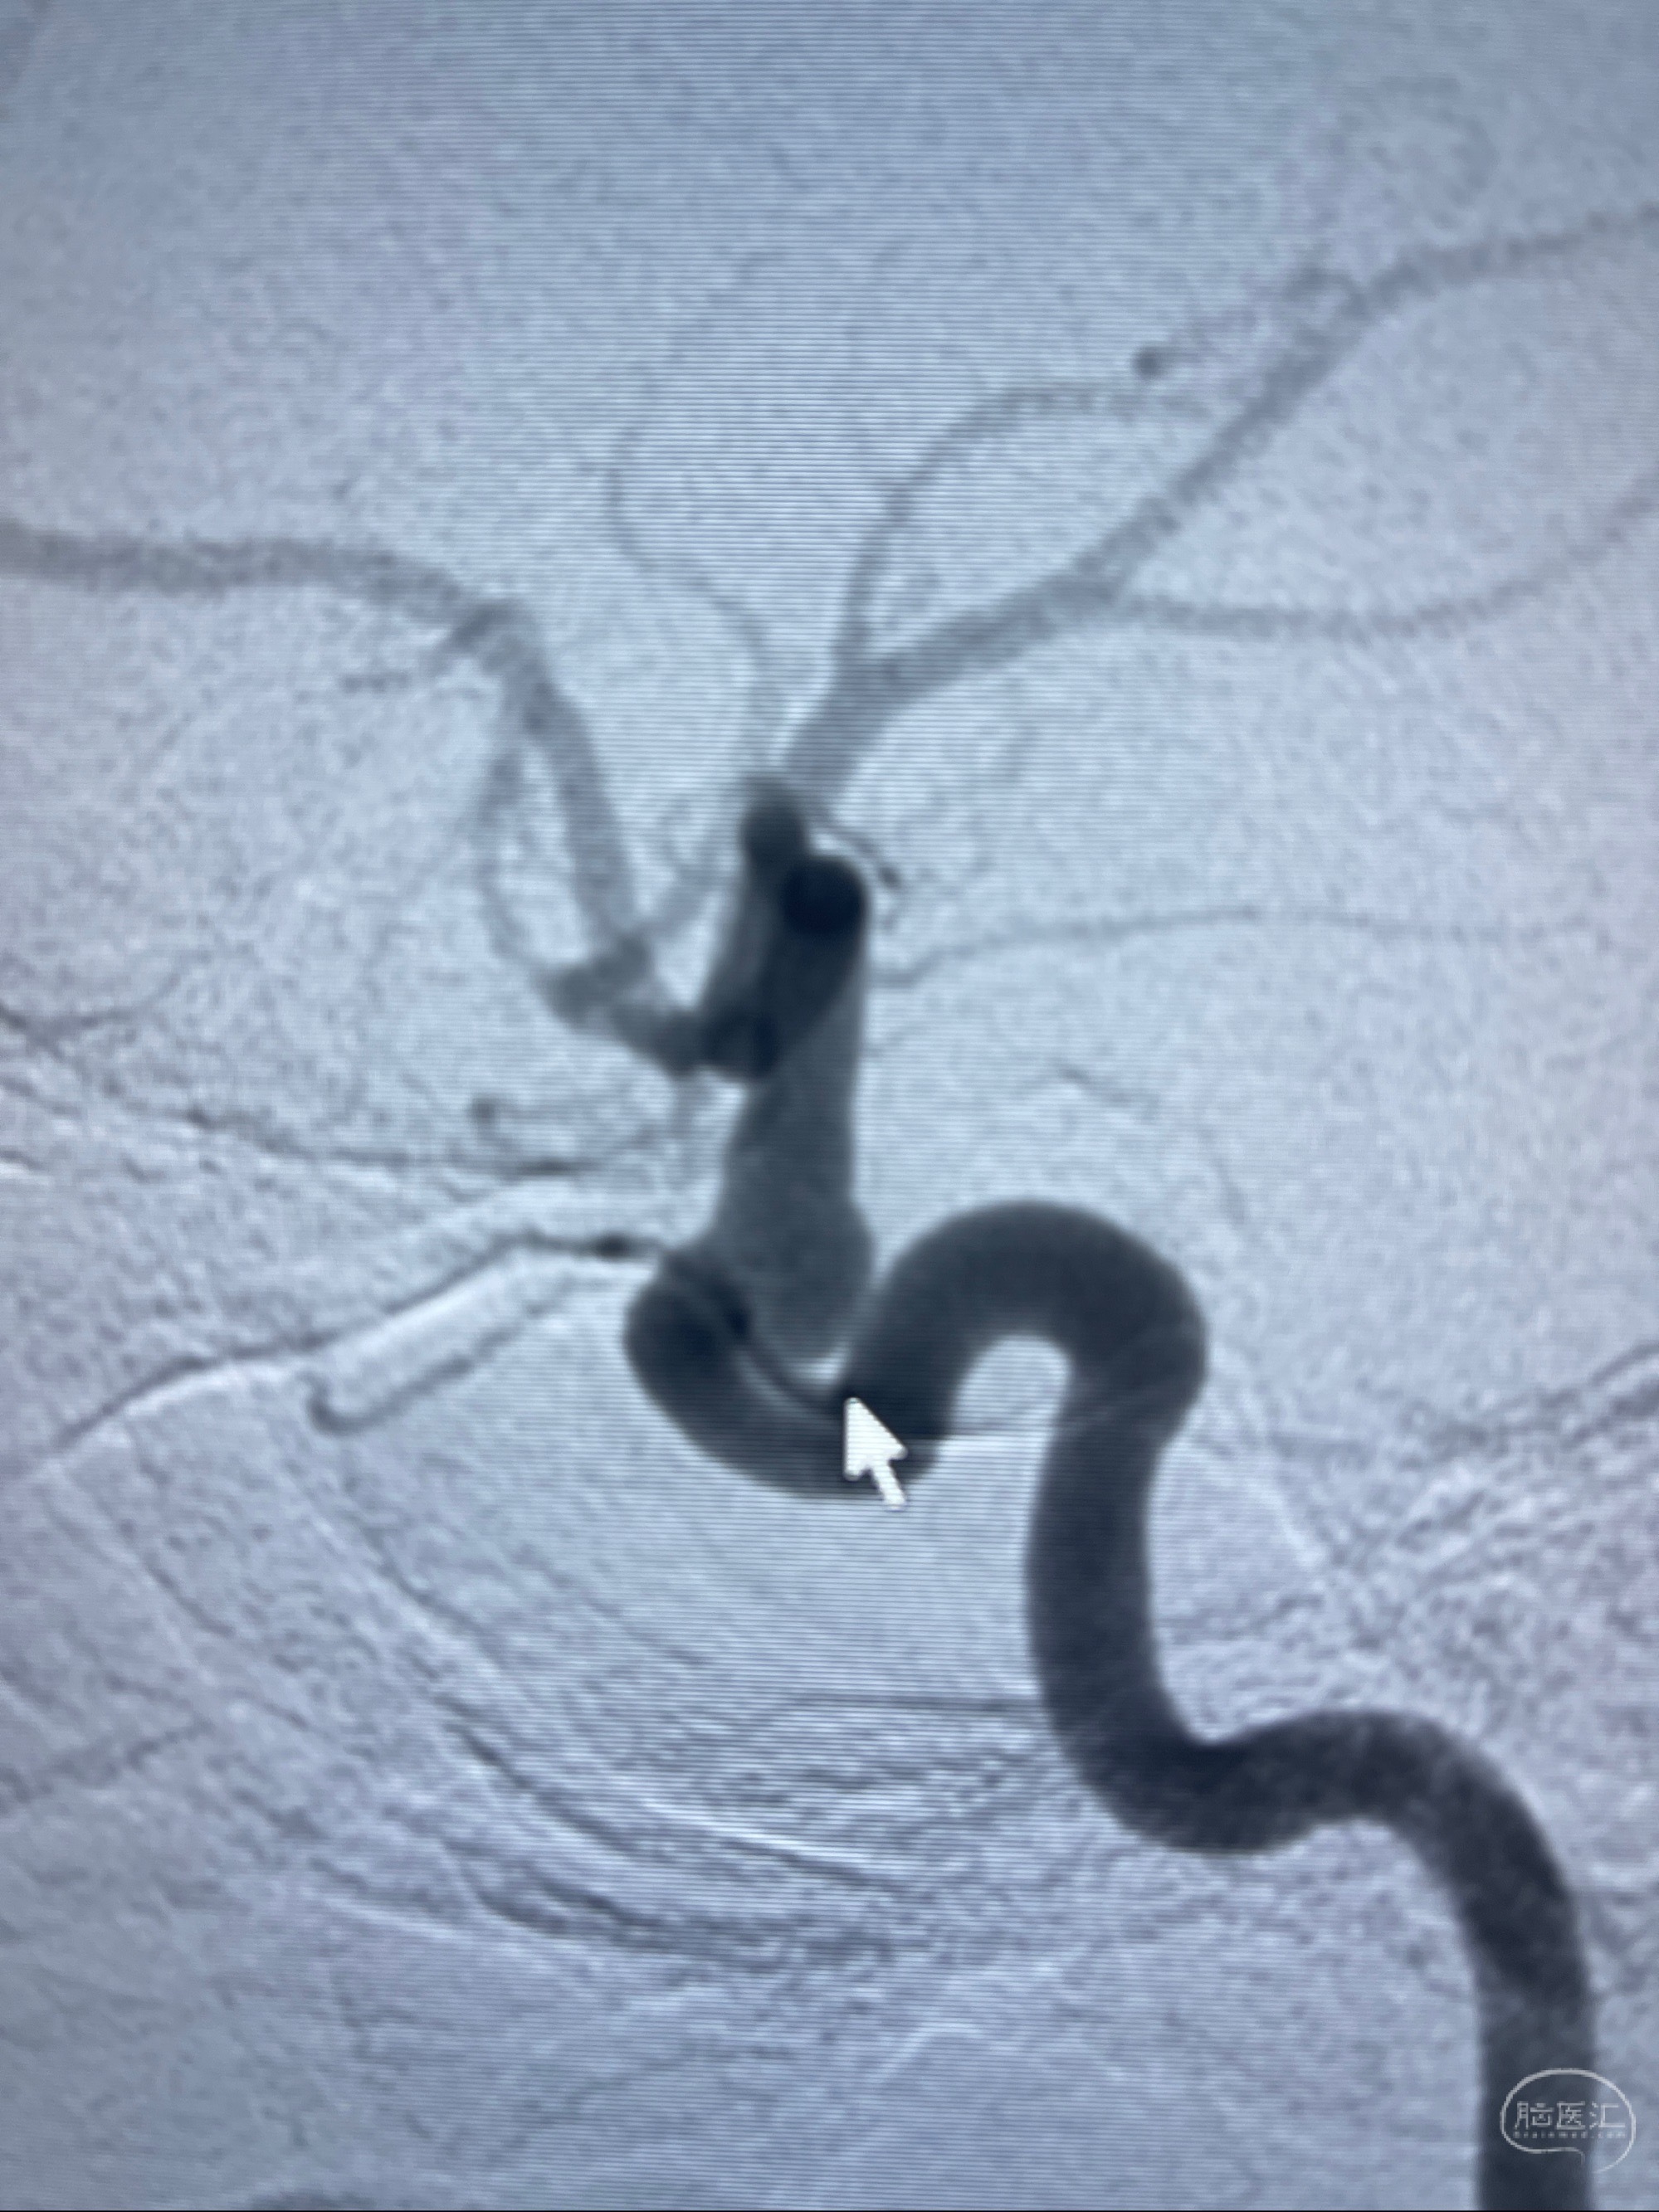

1.右侧颈内动脉眼动脉段动脉瘤

CTA示:右侧颈内动脉C6段见指向下方的突起,余左侧颈内动脉、双侧椎动脉、大脑前动脉、大脑中动脉、大脑后动脉及基底动脉走形正常,未见明显扩张及狭窄,局部未见明显瘤样扩张。

看原图,应该有两侧动脉瘤😅

2023-07-27全脑血管造影:双侧颈内动脉眼动脉段动脉瘤,右侧较大

2023-08-01全麻下行双侧颈眼动脉瘤支架辅助栓塞

- pipeling4.5-20mm

- pipeline 4.0-20mm